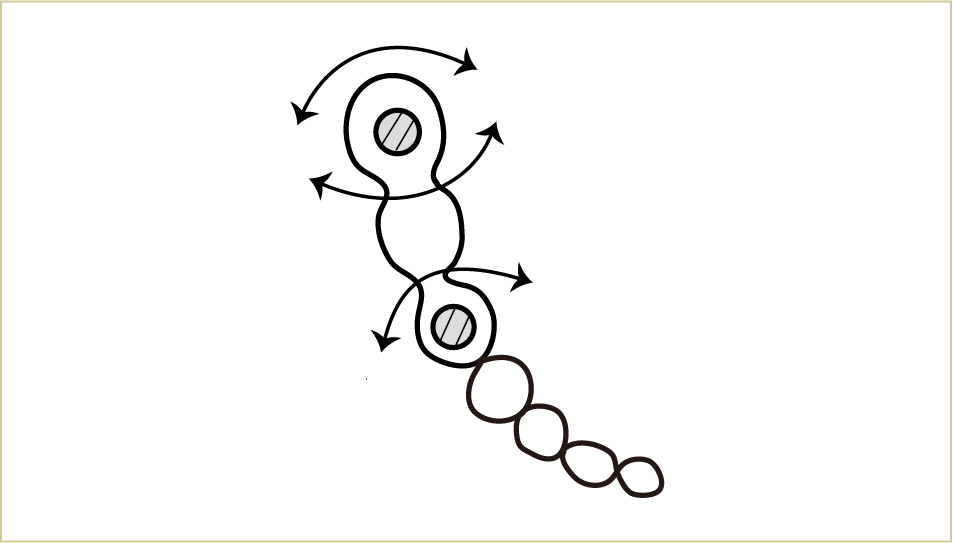

インプラント周囲で、特にブラッシングに注意してほしい所があります。

インプラントによる治療は、うまくいっている場合には自分の歯と見分けがつきづらいものですが、それでも実際には違いがあります。

外から見て周りの歯との違いが分かり難くても、実際には違いがある。それを理解することが長持ちさせるための第1歩となる。

隣同士の歯よりも骨の高さは少し低いことが多く、その分歯肉の厚みが厚いのです。

この歯肉とインプラントが接する部分は、通常の歯と同様に結合している部位もあります。しかしその結合も、全体的には歯と歯肉の付着に比べて弱いものであることがわかっています。

したがって、インプラントの周囲では、歯と歯肉の境目、特に歯肉の中へ歯ブラシの毛先を入れる感覚がより大切になります。

色の部分が汚れないようなイメージを持つことが重要。

歯周病の予防や治療でブラッシングするのと、ほぼ同じイメージで歯ブラシを当てていくことが大切。